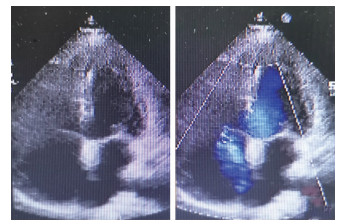

Nuclear receptor corepressor 1 significantly attenuates myocardial infarction injury in mice

QIN Zi-han, CHEN Ying-min, PU Jun

2021, 19(10): 1621-1625,1653. doi: 10.16766/j.cnki.issn.1674-4152.002126

957 8

Abstract:

Objective   To explore the effect of nuclear receptor corepressor 1 (NCoR1) derived from cardiomyocytes on myocardial infarction injury in mice.   Methods   Cardiomyocyte-specific NCoR1 knockout mice were constructed and divided into the sham operation wild-type group, sham operation gene knockout group, myocardial infarction wild-type group and myocardial infarction gene knockout group, with 50 mice in each group. The survival rate and cardiac function level of mice in each group at 28 days of myocardial infarction were statistically analysed. Pathological staining was used to determine the infarct area and fibrosis degree. The levels of serum myocardial enzymes (creatine kinase MB, lactate dehydrogenase) and inflammation indicators (tumor necrosis factor-α, interleukin-6) were determined.   Results   Compared with wild-type mice, the knockout group mice had lower survival rate, significantly decreased left ventricular ejection fraction [(30.39±5.13)% vs. (9.46±2.10)%] and left ventricular shortening fraction [(14.62±2.69)% vs. (4.26±0.96)%], and significantly increased left ventricular volume [(101.50±14.07)μL vs. (197.50±22.41)μL, all P < 0.05]. Small animal PET/CT indicated that wild-type mice had higher intake of 18F-FDG after myocardial infarction [(2.74±0.06)MBq vs. (1.60±0.03)MBq] and degree of infarction [(36.22±0.86)% vs. (47.17±1.27)%] and degree of fibrosis [(32.70±0.85)% vs. (46.38±1.31)%, all P < 0.05]. Serological indicators showed that the myocardial damage of knockout mice was more severe, and the level of inflammation was higher (all P < 0.05).   Conclusion   NCoR1 in cardiomyocytes plays an important protective role in myocardial infarction in mice.